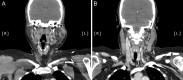

Kimura's disease is a rare disease of unknown aetiology, commonly presenting with slow-growing head and neck subcutaneous nodules, lymphadenopathy, eosinophilia and elevated immunoglobulin E. This report describes a very rare case of a 41-year-old female, of White-British ethnicity, with a new diagnosis of Kimura's disease of the parotid gland and associated cutaneous features. The patient was investigated for 3 years before a diagnosis of Kimura's disease was reached. A superficial parotidectomy was undertaken and no recurrence was observed in the 20 months following surgery. Kimura's disease is easily misdiagnosed, owing to lack of clinical awareness. This case report highlights the troubling symptomatology as well as complexities of diagnosis and management of Kimura's disease. A high level of clinical suspicion is required, for patients of any ethnicity and sex presenting with features consistent with the disease, in order for prompt diagnosis, investigation and management to be achieved.